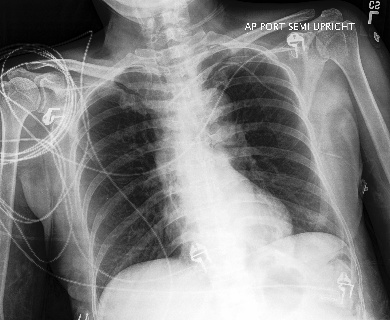

Appendix B More Grad-CAMs of the COVID-CXNet Model with Lung Segmentation Preprocessing

Figure 21: Grad-CAMs from COVID-CXNet with lung segmentation module